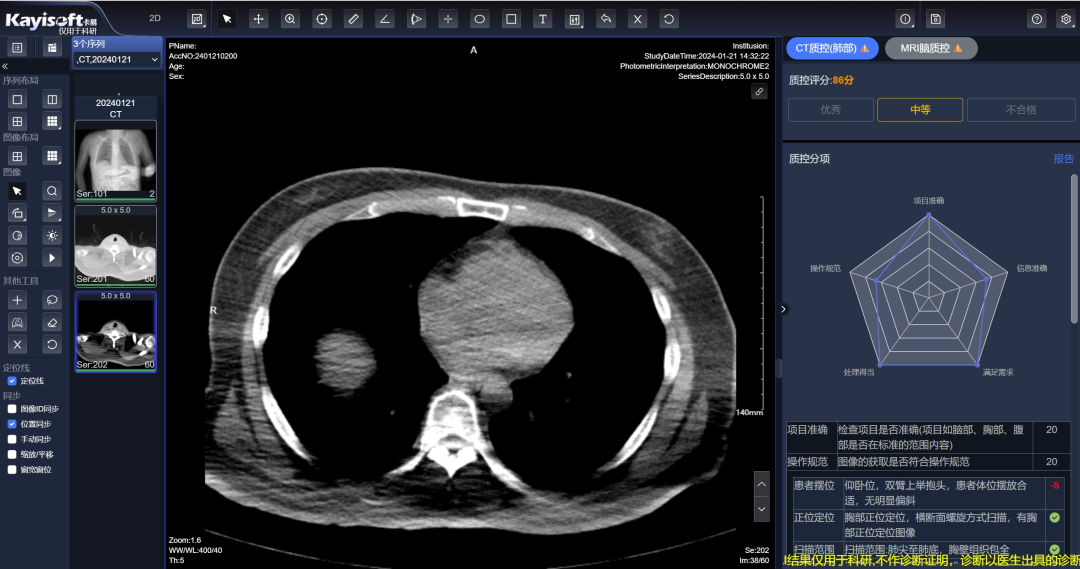

智能影像质控+报告质控

实时监控影像检查质量和报告质量,自动生成质控报告,确保影像数据的准确性和可靠性,从而提高医生诊断的准确性,帮助医疗机构提升管理水平。提供海量影像数据和AI分析工具,助力医疗机构开展临床科研和学术研究。